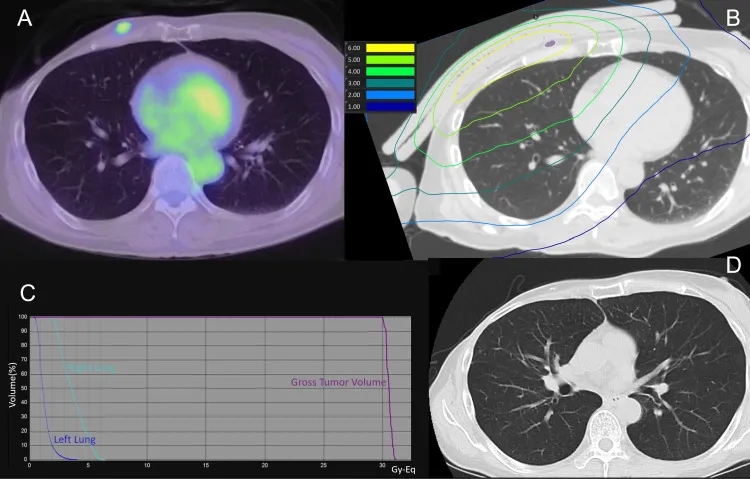

结果显示:BNCT后1天、7天、30天、60天、90天CT扫描,均未显示放射性肺炎迹象。下图3为肺部剂量分布及治疗后90天CT扫描。

▲图源“Cureus”,版权归原作者所有,如无意中侵犯了知识产权,请联系我们删除

①图3 A:治疗前PET-CT。

②图3 B:BNCT(肺部)剂量分布图。

③图3 C:剂量-体积直方图。

④图3 D:治疗后90天CT扫描,显示GTV减少。